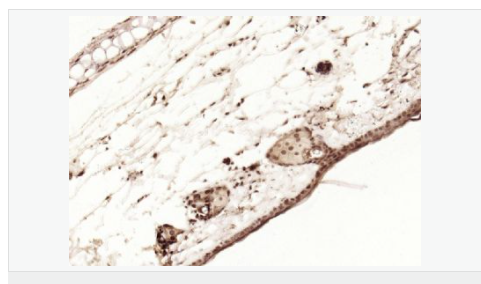

| 產(chǎn)品應(yīng)用 | WB=1:1000-2000 ELISA=1:1000-5000 IHC-P=1:100-500 IHC-F=1:100-500 Flow-Cyt=1ug/Test ICC=1:100-500 IF=1:100-500 (石蠟切片需做抗原修復(fù)) not yet tested in other applications. optimal dilutions/concentrations should be determined by the end user. |

| 產(chǎn)品介紹 | p53, a DNA-binding, oligomerization domain- and transcription activation domain-containing tumor suppressor, upregulates growth arrest and apoptosis-related genes in response to stress signals, thereby influencing programmed cell death, cell differentiation, and cell cycle control mechanisms. p53 localizes to the nucleus, yet can be chaperoned to the cytoplasm by the negative regulator, MDM2. MDM2 is an E3 ubiquitin ligase that is upregulated in the presence of active p53, where it poly-ubiquitinates p53 for proteasome targeting. p53 fluctuates between latent and active DNA-binding conformations and is differentially activated through posttranslational modifications, including phosphorylation and acetylation. Mutations in the DNA-binding domain (DBD) of p53, amino acids 110-286, can compromise energetically-favorable association with cis elements and are implicated in several human cancers. Function: [FUNCTION] Acts as a tumor suppressor in many tumor types; induces growth arrest or apoptosis depending on the physiological circumstances and cell type. Involved in cell cycle regulation as a trans-activator that acts to negatively regulate cell division by controlling a set of genes required for this process. One of the activated genes is an inhibitor of cyclin-dependent kinases. Apoptosis induction seems to be mediated either by stimulation of BAX and FAS antigen expression, or by repression of Bcl-2 expression. Implicated in Notch signaling cross-over. Prevents CDK7 kinase activity when associated to CAK complex in response to DNA damage, thus stopping cell cycle progression. Isoform 2 enhances the transactivation activity of isoform 1 from some but not all TP53-inducible promoters. Isoform 4 suppresses transactivation activity and impairs growth suppression mediated by isoform 1. Isoform 7 inhibits isoform 1-mediated apoptosis. Subunit: Interacts with AXIN1. Probably part of a complex consisting of TP53, HIPK2 and AXIN1 (By similarity). Binds DNA as a homotetramer. Interacts with histone acetyltransferases EP300 and methyltransferases HRMT1L2 and CARM1, and recruits them to promoters Subcellular Location: Cytoplasm. Nucleus. Nucleus, PML body. Endoplasmic reticulum. Note=Interaction with BANP promotes nuclear localization. Recruited into PML bodies together with CHEK2. Tissue Specificity: Ubiquitous. Isoforms are expressed in a wide range of normal tissues but in a tissue-dependent manner. Isoform 2 is expressed in most normal tissues but is not detected in brain, lung, prostate, muscle, fetal brain, spinal cord and fetal liver. Isoform 3 is expressed in most normal tissues but is not detected in lung, spleen, testis, fetal brain, spinal cord and fetal liver. Isoform 7 is expressed in most normal tissues but is not detected in prostate, uterus, skeletal muscle and breast. Isoform 8 is detected only in colon, bone marrow, testis, fetal brain and intestine. Isoform 9 is expressed in most normal tissues but is not detected in brain, heart, lung, fetal liver, salivary gland, breast or intestine. Post-translational modifications: Acetylated. Acetylation of Lys-382 by CREBBP enhances transcriptional activity. Deacetylation of Lys-382 by SIRT1 impairs its ability to induce proapoptotic program and modulate cell senescence. Phosphorylation on Ser residues mediates transcriptional activation. Phosphorylated by HIPK1. Phosphorylation at Ser-9 by HIPK4 increases repression activity on BIRC5 promoter. Phosphorylated on Thr-18 by VRK1. Phosphorylated on Ser-20 by CHEK2 in response to DNA damage, which prevents ubiquitination by MDM2. Phosphorylated on Ser-20 by PLK3 in response to reactive oxygen species (ROS), promoting p53/TP53-mediated apoptosis. Phosphorylated on Thr-55 by TAF1, which promotes MDM2-mediated degradation. Phosphorylated on Ser-33 by CDK7 in a CAK complex in response to DNA damage. Phosphorylated on Ser-46 by HIPK2 upon UV irradiation. Phosphorylation on Ser-46 is required for acetylation by CREBBP. Phosphorylated on Ser-392 following UV but not gamma irradiation. Phosphorylated upon DNA damage, probably by ATM or ATR. Phosphorylated on Ser-15 upon ultraviolet irradiation; which is enhanced by interaction with BANP. Phosphorylated by NUAK1 at Ser-15 and Ser-392; was initially thought to be mediated by STK11/LKB1 but it was later shown that it is indirect and that STK11/LKB1-dependent phosphorylation is probably mediated by downstream NUAK1 (PubMed:21317932). It is unclear whether AMP directly mediates phosphorylation at Ser-15. Phosphorylated on Thr-18 by isoform 1 and isoform 2 of VRK2. Phosphorylation on Thr-18 by isoform 2 of VRK2 results in a reduction in ubiquitination by MDM2 and an increase in acetylation by EP300. Stabilized by CDK5-mediated phosphorylation in response to genotoxic and oxidative stresses at Ser-15, Ser-33 and Ser-46, leading to accumulation of p53/TP53, particularly in the nucleus, thus inducing the transactivation of p53/TP53 target genes. Phosphorylated at Ser-315 and Ser-392 by CDK2 in response to DNA-damage. Dephosphorylated by PP2A-PPP2R5C holoenzyme at Thr-55. SV40 small T antigen inhibits the dephosphorylation by the AC form of PP2A. May be O-glycosylated in the C-terminal basic region. Studied in EB-1 cell line. Ubiquitinated by MDM2 and SYVN1, which leads to proteasomal degradation. Ubiquitinated by RFWD3, which works in cooperation with MDM2 and may catalyze the formation of short polyubiquitin chains on p53/TP53 that are not targeted to the proteasome. Ubiquitinated by MKRN1 at Lys-291 and Lys-292, which leads to proteasomal degradation. Deubiquitinated by USP10, leading to its stabilization. Ubiquitinated by TRIM24, which leads to proteasomal degradation. Ubiquitination by TOPORS induces degradation. Deubiquitination by USP7, leading to stabilization. Isoform 4 is monoubiquitinated in an MDM2-independent manner. Monomethylated at Lys-372 by SETD7, leading to stabilization and increased transcriptional activation. Monomethylated at Lys-370 by SMYD2, leading to decreased DNA-binding activity and subsequent transcriptional regulation activity. Lys-372 monomethylation prevents interaction with SMYD2 and subsequent monomethylation at Lys-370. Dimethylated at Lys-373 by EHMT1 and EHMT2. Monomethylated at Lys-382 by SETD8, promoting interaction with L3MBTL1 and leading to repress transcriptional activity. Demethylation of dimethylated Lys-370 by KDM1A prevents interaction with TP53BP1 and represses TP53-mediated transcriptional activation. Sumoylated by SUMO1. DISEASE: Note=TP53 is found in increased amounts in a wide variety of transformed cells. TP53 is frequently mutated or inactivated in about 60% of cancers. TP53 defects are found in Barrett metaplasia a condition in which the normally stratified squamous epithelium of the lower esophagus is replaced by a metaplastic columnar epithelium. The condition develops as a complication in approximately 10% of patients with chronic gastroesophageal reflux disease and predisposes to the development of esophageal adenocarcinoma. Similarity: Belongs to the p53 family. SWISS: P04637 Gene ID: 7157 Database links: Entrez Gene: 7157 Human Entrez Gene: 22059 Mouse Omim: 191170 Human SwissProt: P04637 Human SwissProt: P02340 Mouse Unigene: 654481 Human Unigene: 222 Mouse Unigene: 54443 Rat Important Note: This product as supplied is intended for research use only, not for use in human, therapeutic or diagnostic applications. |